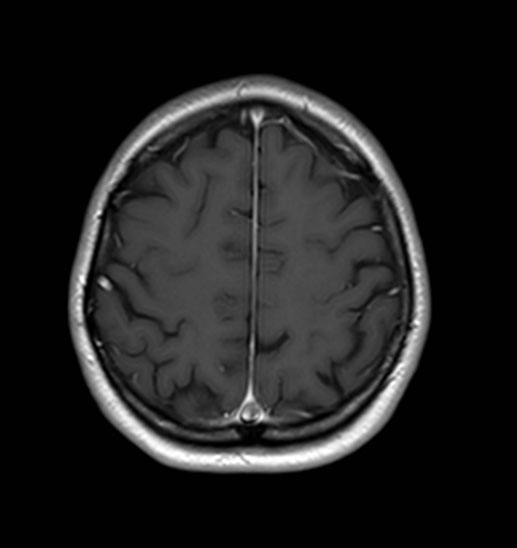

Magnetic resonance imaging after six months (Figure 5) showed stability of the meningioma with re-expansion of the superior sagittal sinus comparing with the MRI before LP shunt placement. At the present time the patient has not been treated by radiosurgery because she is doing well without symptoms and the lesion is stable.

Figure 5: Gadolinium-enhanced T1 MRI in axial section. Left side corresponds with the first MRI and right side with the MRI after six months. We can observe meningioma stability with partial re-expansion of the superior sagittal sinus in the posterior third comparing both studies.

Share Image: